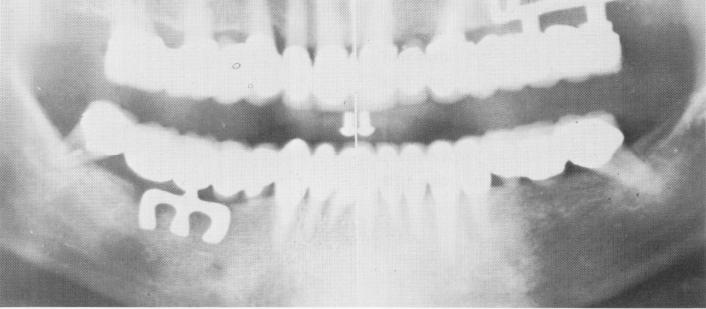

Fig. 11-67. The final Panorex of the completed case.

After the prostheses were worn for about 5 days, they were removed and the tissues checked for any pontic impingement. All necessary adjustments were made. The teeth and the two full arch prostheses were then thoroughly cleansed and dried before final cementation. A final check was made of the occlusion (Fig. 11-66), and a Panorex of the entire jaw was taken (Fig. 11-67).